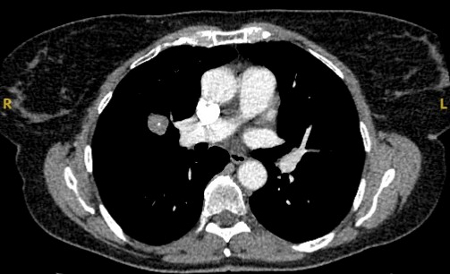

Solid nodules: volume doubling time of >600 days does not require follow-up, while a volume doubling time of <400 days, or clear growth defined as an increase in volume of 25% or more, suggests diagnostic investigations are required.[Figure caption and citation for the preceding image starts]: Computed tomography (CT) showing a right upper lobe spiculated solitary nodule within emphysema, in a current smoker with previous asbestos exposure. Note the visible pleural plaque on the left side. Resection histology revealed adenocarcinoma of the lungFrom the collection of Dr George Tsaknis, MD, PhD, FRCP(London), MRQA, MAcadMEd, PGCert; used with permission [Citation ends].

Upper and middle lobe solitary pulmonary nodules have a likelihood ratio for malignancy of 1.2 to 1.6.[19][32] The upper lobe location has been shown to be an independent predictor of malignancy.[21]

The appearance of the adjacent fissure, as well as any visible pleural ‘tags’, are signs that need to be considered when evaluating perifissural or peripheral solitary lung nodules. A retracted fissure associated with a non-smooth nodule increases the possibility of malignancy.[33][34][Figure caption and citation for the preceding image starts]: Computed tomography (CT) sections from two cases with benign perifissural nodules. Note the smooth margins and the normal undisturbed adjacent fissureFrom the collection of Dr George Tsaknis, MD, PhD, FRCP(London), MRQA, MAcadMEd, PGCert; used with permission [Citation ends].